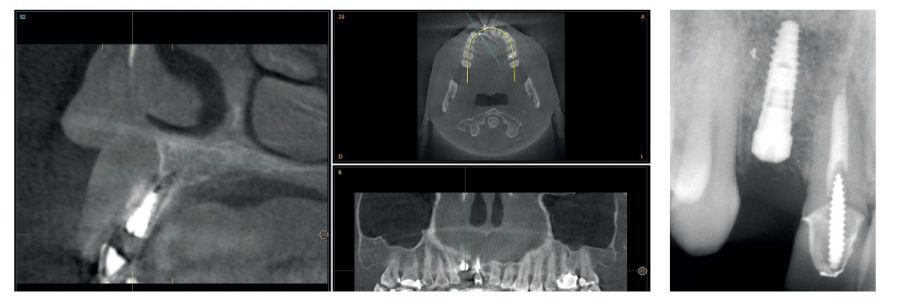

Four months later, a new dental cone-beam is performed to quantify the gain obtained in width with the regenerative procedure. It is observed in the sectional cut that a crest width of more than 7 mm and a complete regeneration of the alveolar ridge has been achieved, allowing the insertion of a new dental implant in the adequate position (Figure 10). In the surgical reentry, the information of the Cone-Beam is verified with a total integration of the graft material, as shown in the clinical images at the time of lifting the flap for the insertion of the implant (Figures 11 and 12). The microscrew is removed and the implant is placed, which is performed by vestibular compression of the graft to gain in this manner even more contour in this area (Figure 13). The implant is left in a surgical phase, with a low healing abutment that allows a subsequent location of the same without an aggressive soft tissue surgery when the construction of the prosthesis is initiated. The provisional crown remains as an extension from the tooth 1.1.

Three months later, the prosthetic phase begins. The state of the gingival tissue is correct, although at vestibular level we would like to achieve a decrease of the zenith of the future tooth, so a connective tissue graft is planned that allows this more appropriate emergence profile conformation. The case ends with E-max crowns at the level of 1.2 and 1.1, achieving a harmonious smile and fully integrated in the rest of the smile, regarding colour, emergence and disposition of the gingival margins (Figures 14-15). The patient continues a follow up for years, maintaining the stability of the performed rehabilitation (Figure 16).